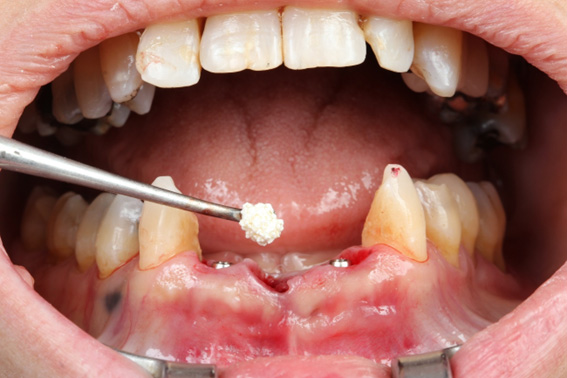

8 | Nanosynt to fill the gaps and reconstruct the area